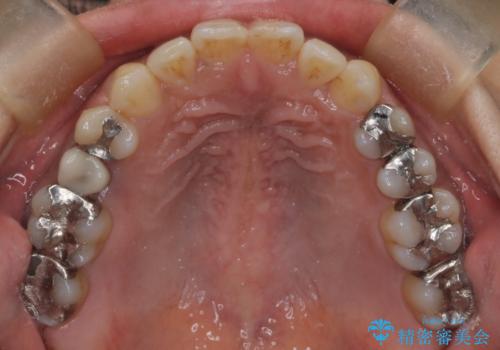

【インビザライン】前歯の凸凹をなおしたい

- 前歯の凸凹を主訴に来院されました。

インビザライン にて治療を行い、歯並びの改善を行うことができました。